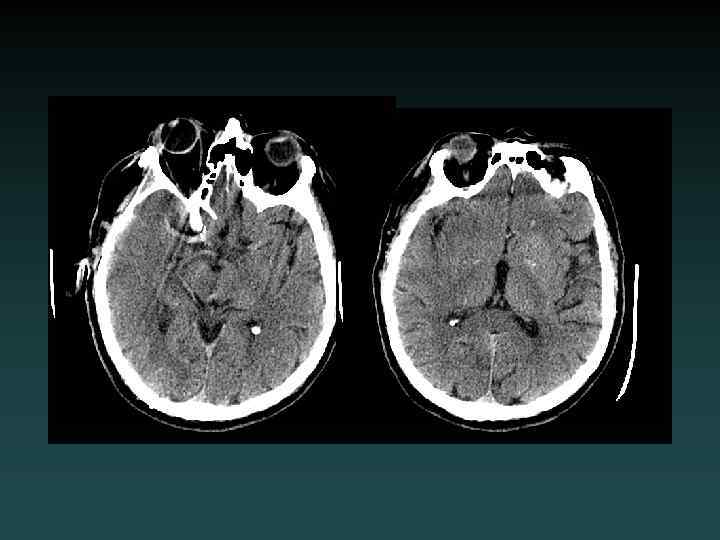

Anoxic brain injury • Loss of Gray-White • Progresses with worsening edema • Pseudo. SAH • Hydrocephalus • Cisterns compressed